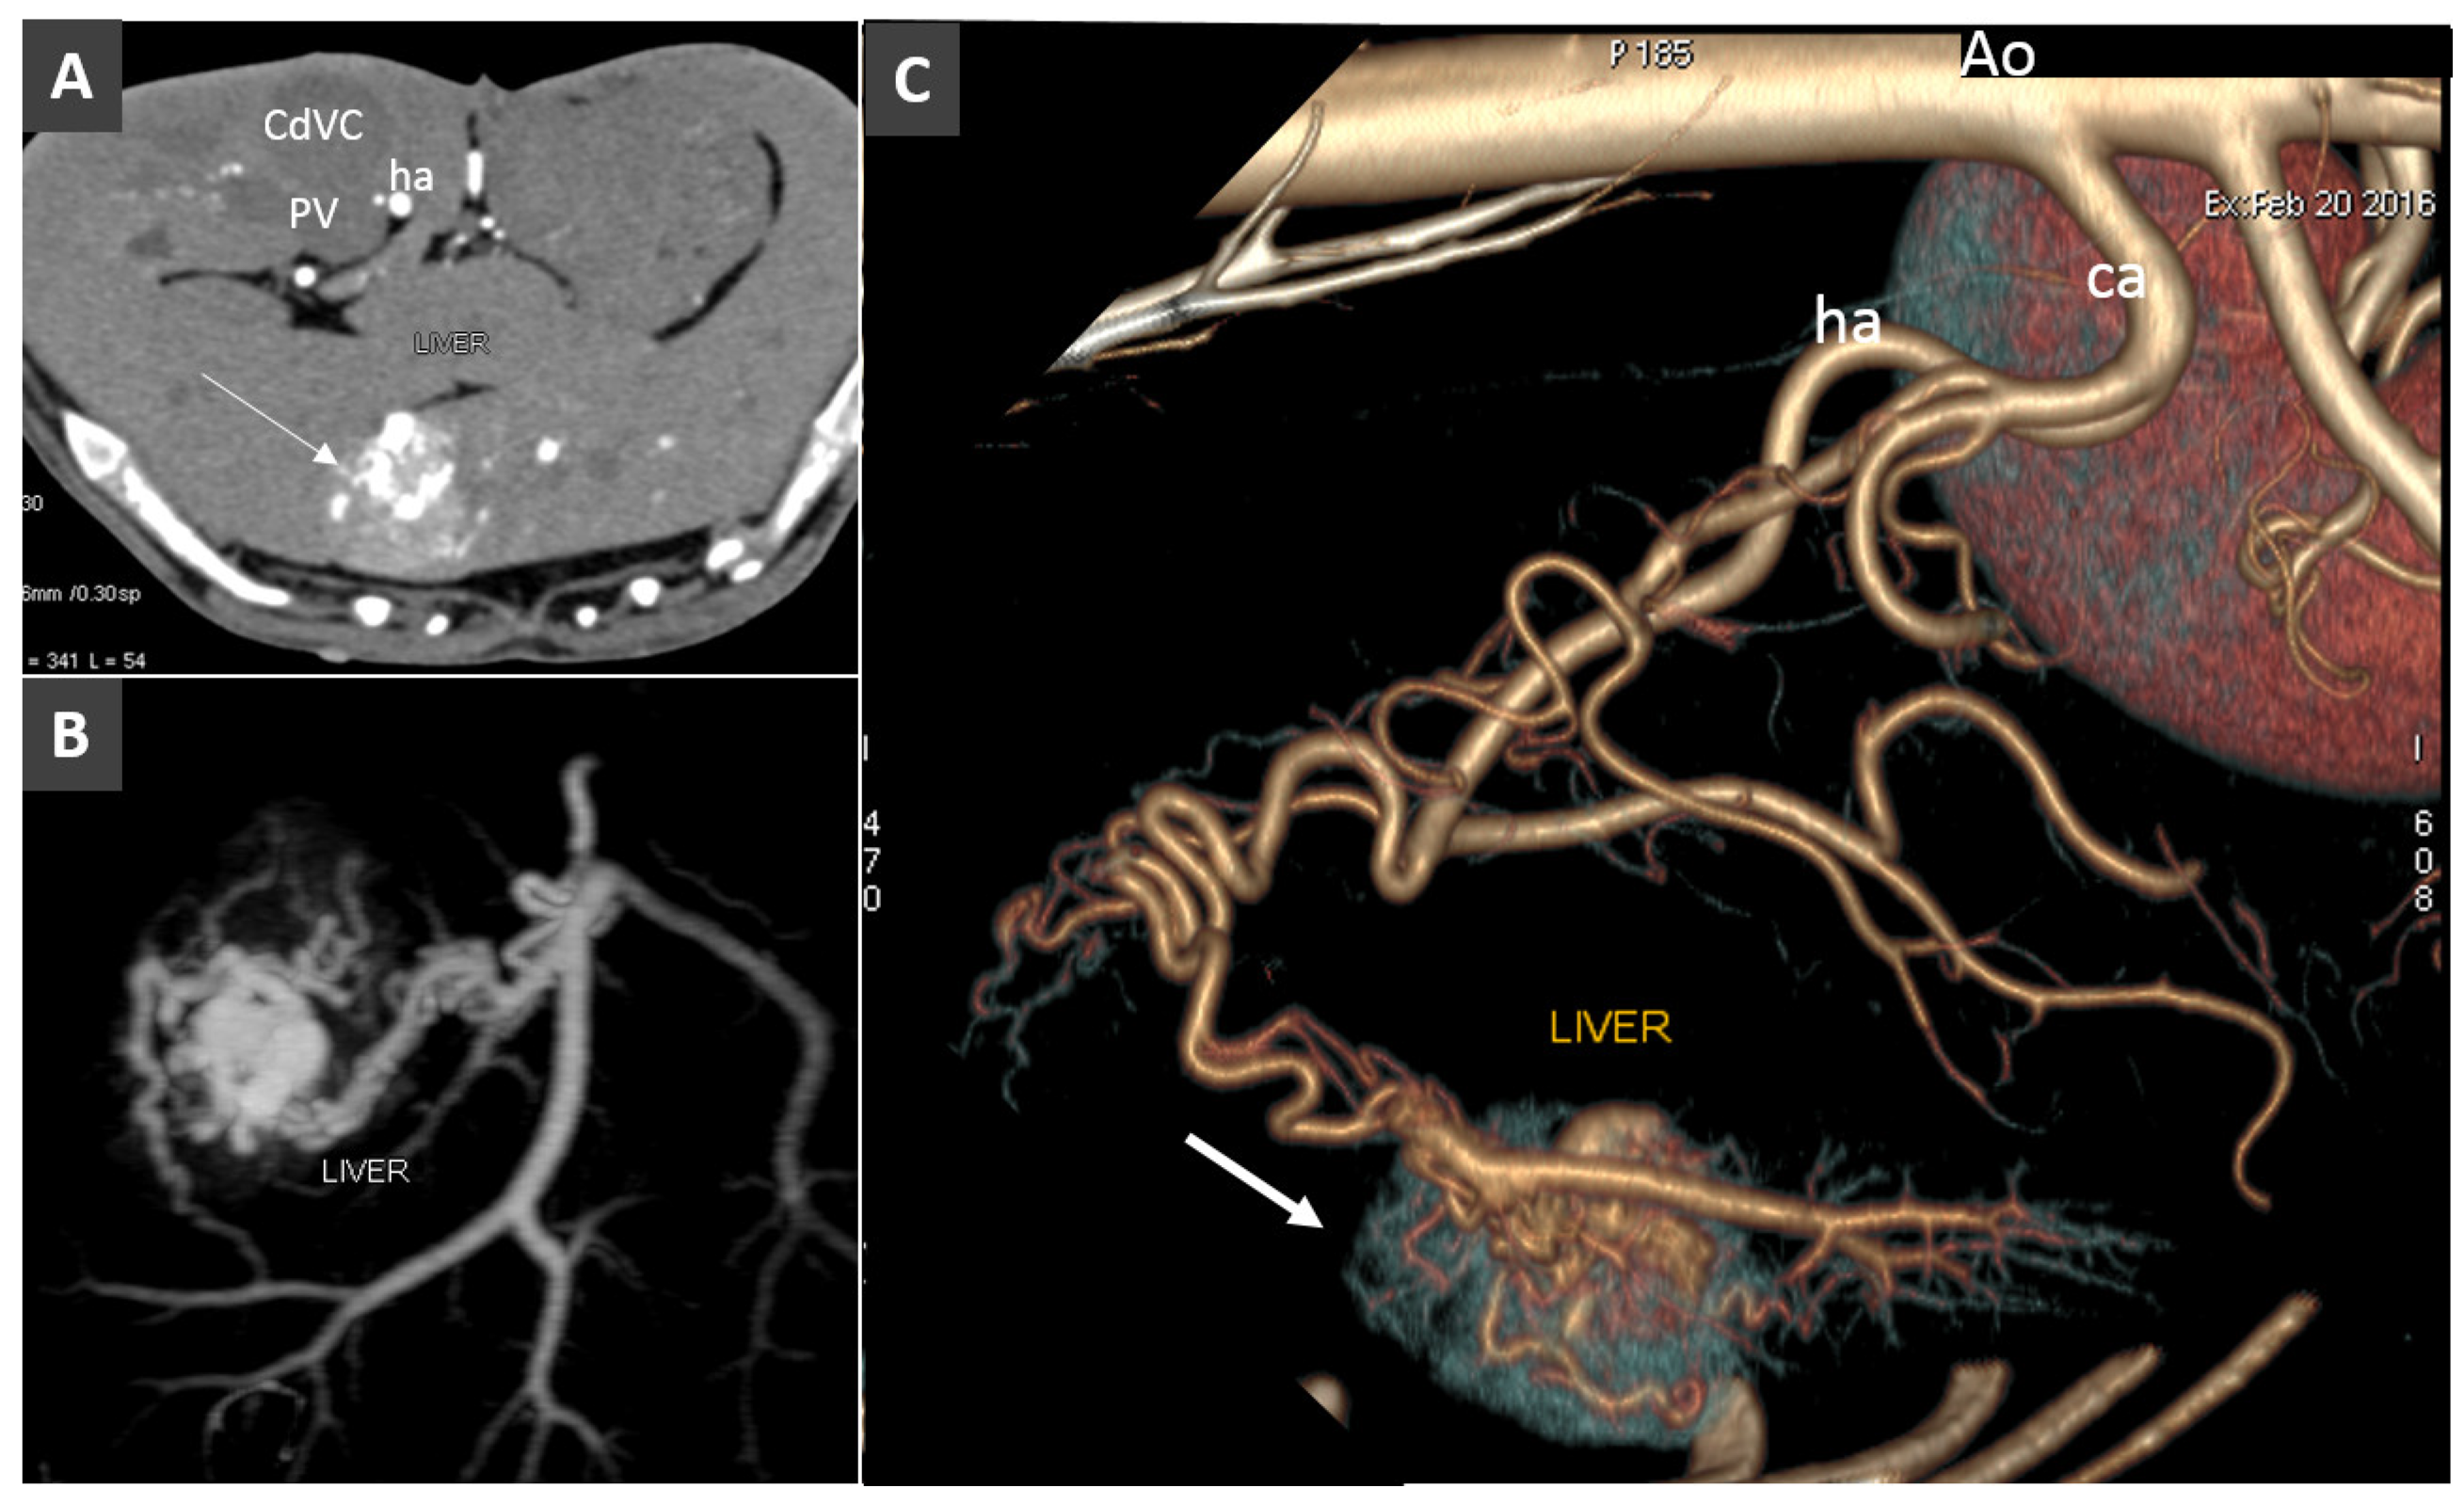

- Zwingenberger, A.L.; McLear, R.C.; Weisse, C. Diagnosis of arterioportal fistulae in four dogs using computed tomographic angiography. Vet. Radiol. Ultrasound 2005, 46, 472–477. [Google Scholar] [CrossRef]

- Specchi, S.; Rossi, F.; Weisse, C.; Morabito, S.; Petrovitch, N.P.; Drees, R.; Thierry, F.; Ricciardi, M.; Penchome, R.; Armenise, A.; et al. Canine and feline abdominal arterioportal communications can be classified based on branching patterns in computed tomographic angiography. Vet. Radiol. Ultrasound 2018, 59, 687–696. [Google Scholar] [CrossRef] [PubMed]

- Weisse, C. Hepatic Arteriovenous Malformations (AVMs) and Fistulas. In Veterinary Image-Guided Interventions; Weisse, C., Berent, A., Eds.; John Wiley & Sons, Ltd.: Oxford, UK, 2015. [Google Scholar]